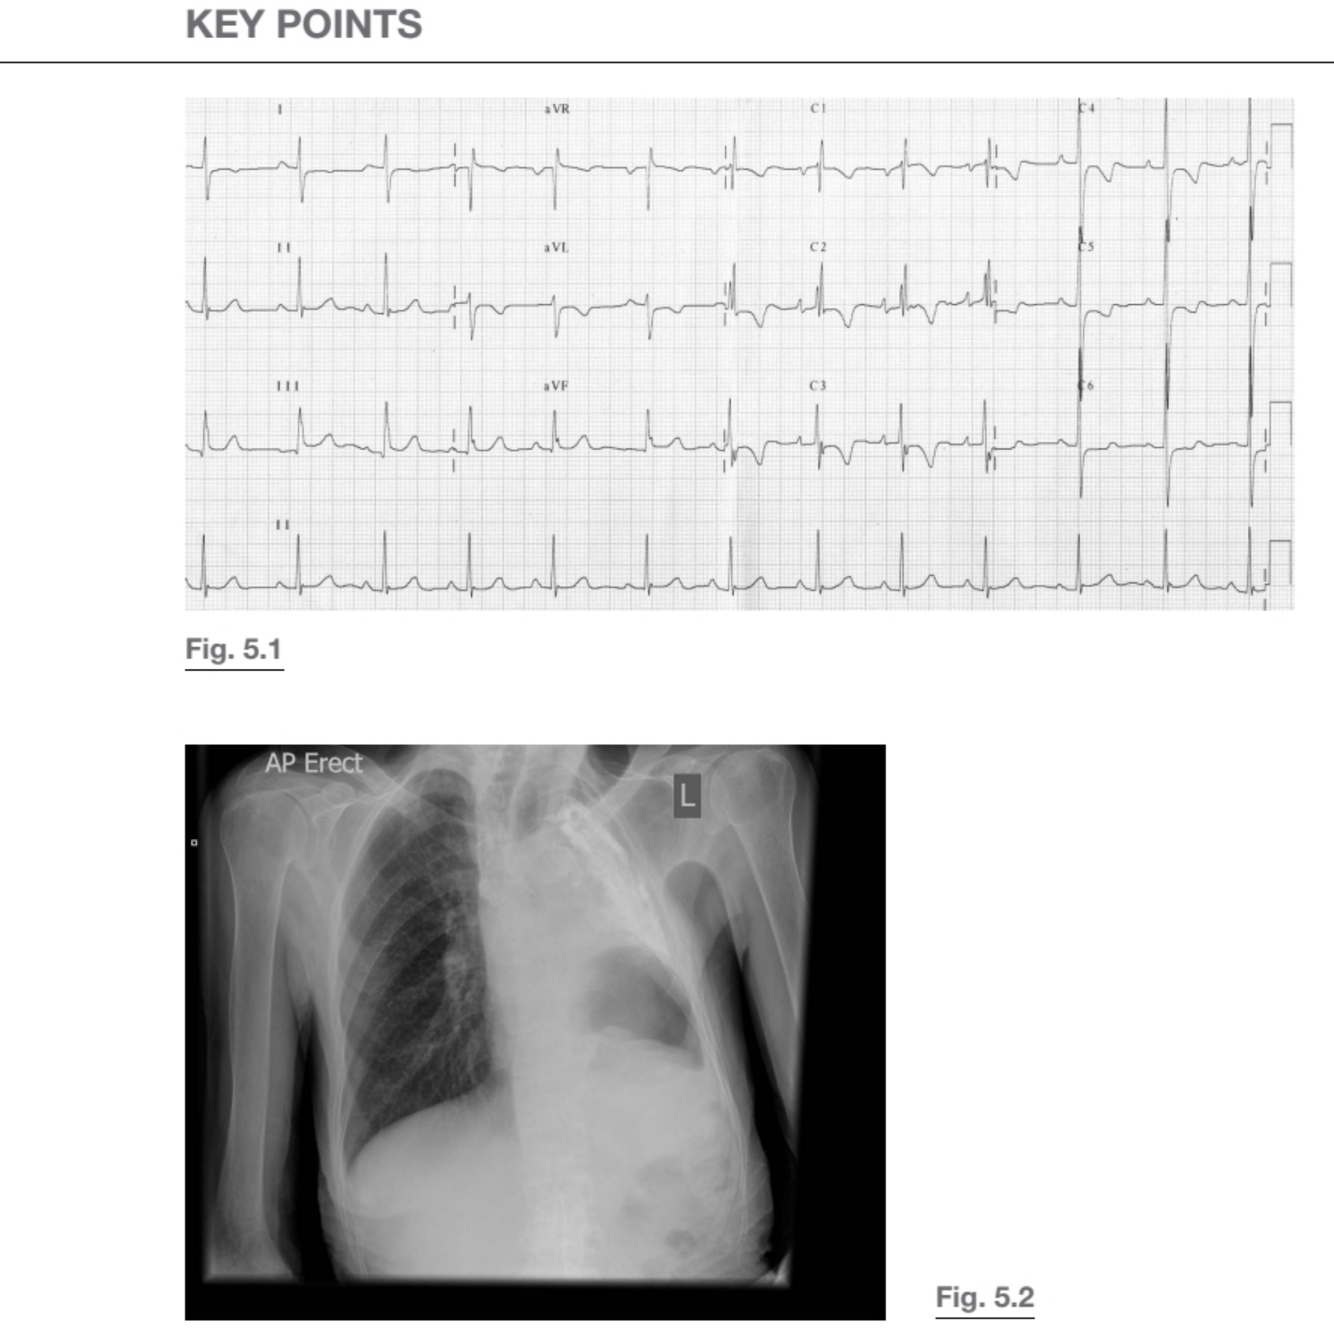

ecG

• PR interval is at the upper limit of normal (200 msec)

• Tall R waves in lateral leads V5 and V6 with mild ST segment depression

suggests left ventricular hypertrophy

• rSR pattern in V1 with T wave inversion in V1–V3, suggestive of right

bundle branch block